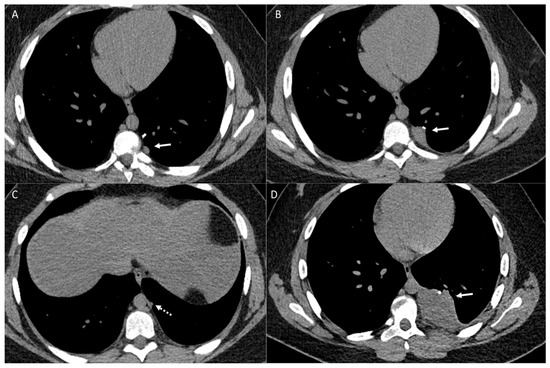

2. The Lungs

2.1. Parenchymal Metastasis

2.2. Vascular Metastasis

2.3. Endobronchial Metastasis

2.4. Lymphangitic Carcinomatosis